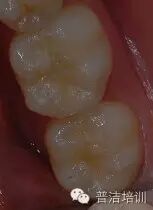

备洞

选择性酸蚀

涂布自酸蚀粘结剂

此步骤与常规备洞相同。

印章覆盖成形

要点:

1、若龋洞较深,分层充填,在最后的一层树脂固化前覆盖印章

2、 若龋洞较浅,可单层充填

3 、树脂不宜过多,否则影响形态恢复的准确性,并为调牙合带来困难,影响充填效果

初步完成